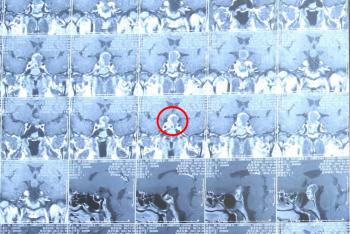

颅咽管瘤患者MRI